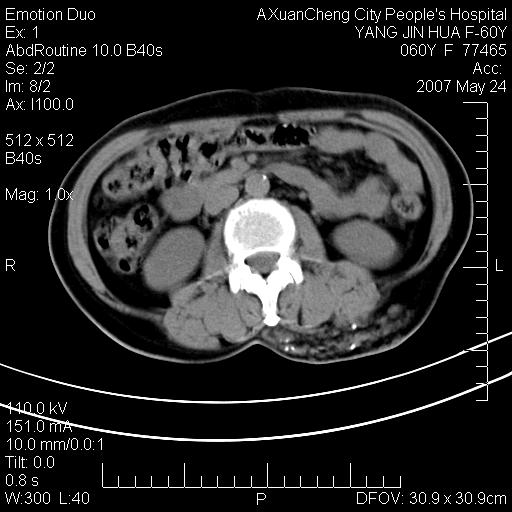

发现左侧腰背部包块40余年,逐渐长大,质软,局部表面可见扩张的血管影

左背部皮下良性肿瘤,密度不均,边界不清,内有脂肪、钙化,增强扫描无明显强化,血管平滑肌脂肪瘤?进一步诊断有困难,建议穿刺活检。

左侧背部皮下混杂密度肿块,结构较疏松,边缘欠光整,内有多发斑点状钙化,考虑:皮下血管瘤。

这个病理增强扫描之前,我们是考虑是血管瘤,可是现在增强后一点强化都没有,还能考虑是血管瘤吗